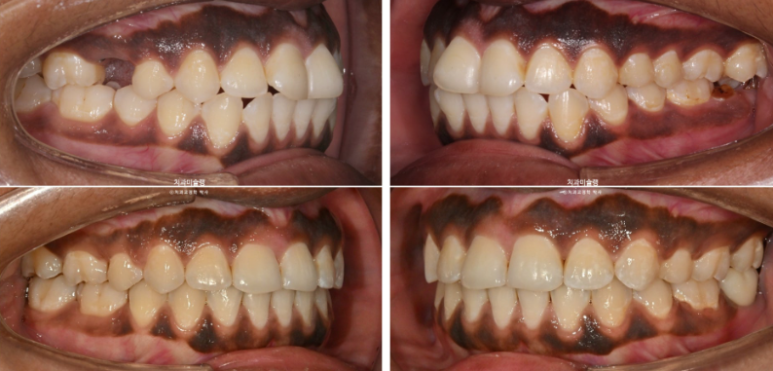

The maxillary and mandibular midlines are well aligned,

and the molar occlusion demonstrates a tight Class I relationship with no spacing.We will now review the before-and-after comparison.

2023.07-2025.12

The treatment, including implant placement, was completed with a clean and stable result.

23.07~25.12

With the protruded anterior teeth corrected, the smile appears much more refined and harmonious.

The lip protrusion has also been resolved.